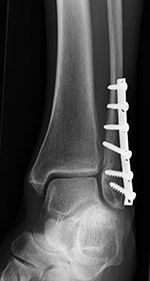

Locking low contact dynamic compression plate and screws with two fully threaded syndesmotic screws |

Dynamic compression plate and syndesmotic screws as well as two fully threaded cortical medial malleolus screws